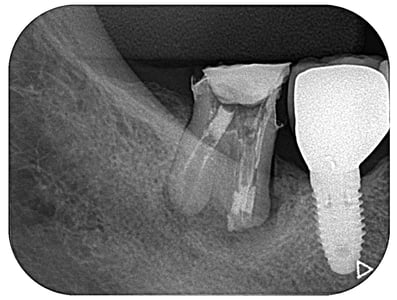

#穿孔修復

”穿孔”とは、簡単に言えば、歯の中に異常な”穴”が開いていることです。通常なら明らかに抜歯と診断されても不思議ではない症例ですが、時間をかけて修復しました。奥は他院で行ったインプラントですが、問題なく機能しています。

治療期間:約6ケ月

治療回数:11回(1~2回/月)

治療費:30万円(穿孔修復+根管治療+支台築造+セラミックス・クラウン)※毎回の処置料は別途

リスク:再治療は困難なこと。

※リスクはどのような治療にも必ずあること。

(そもそも抜歯の症例)

※この症例はのちに、根管外から穿孔部を再封鎖しました。

治療後2.5年経過しました。(2022年4月04日時点)

力及ばず、残念ながら、2023(R5)年4月 抜歯になりました。